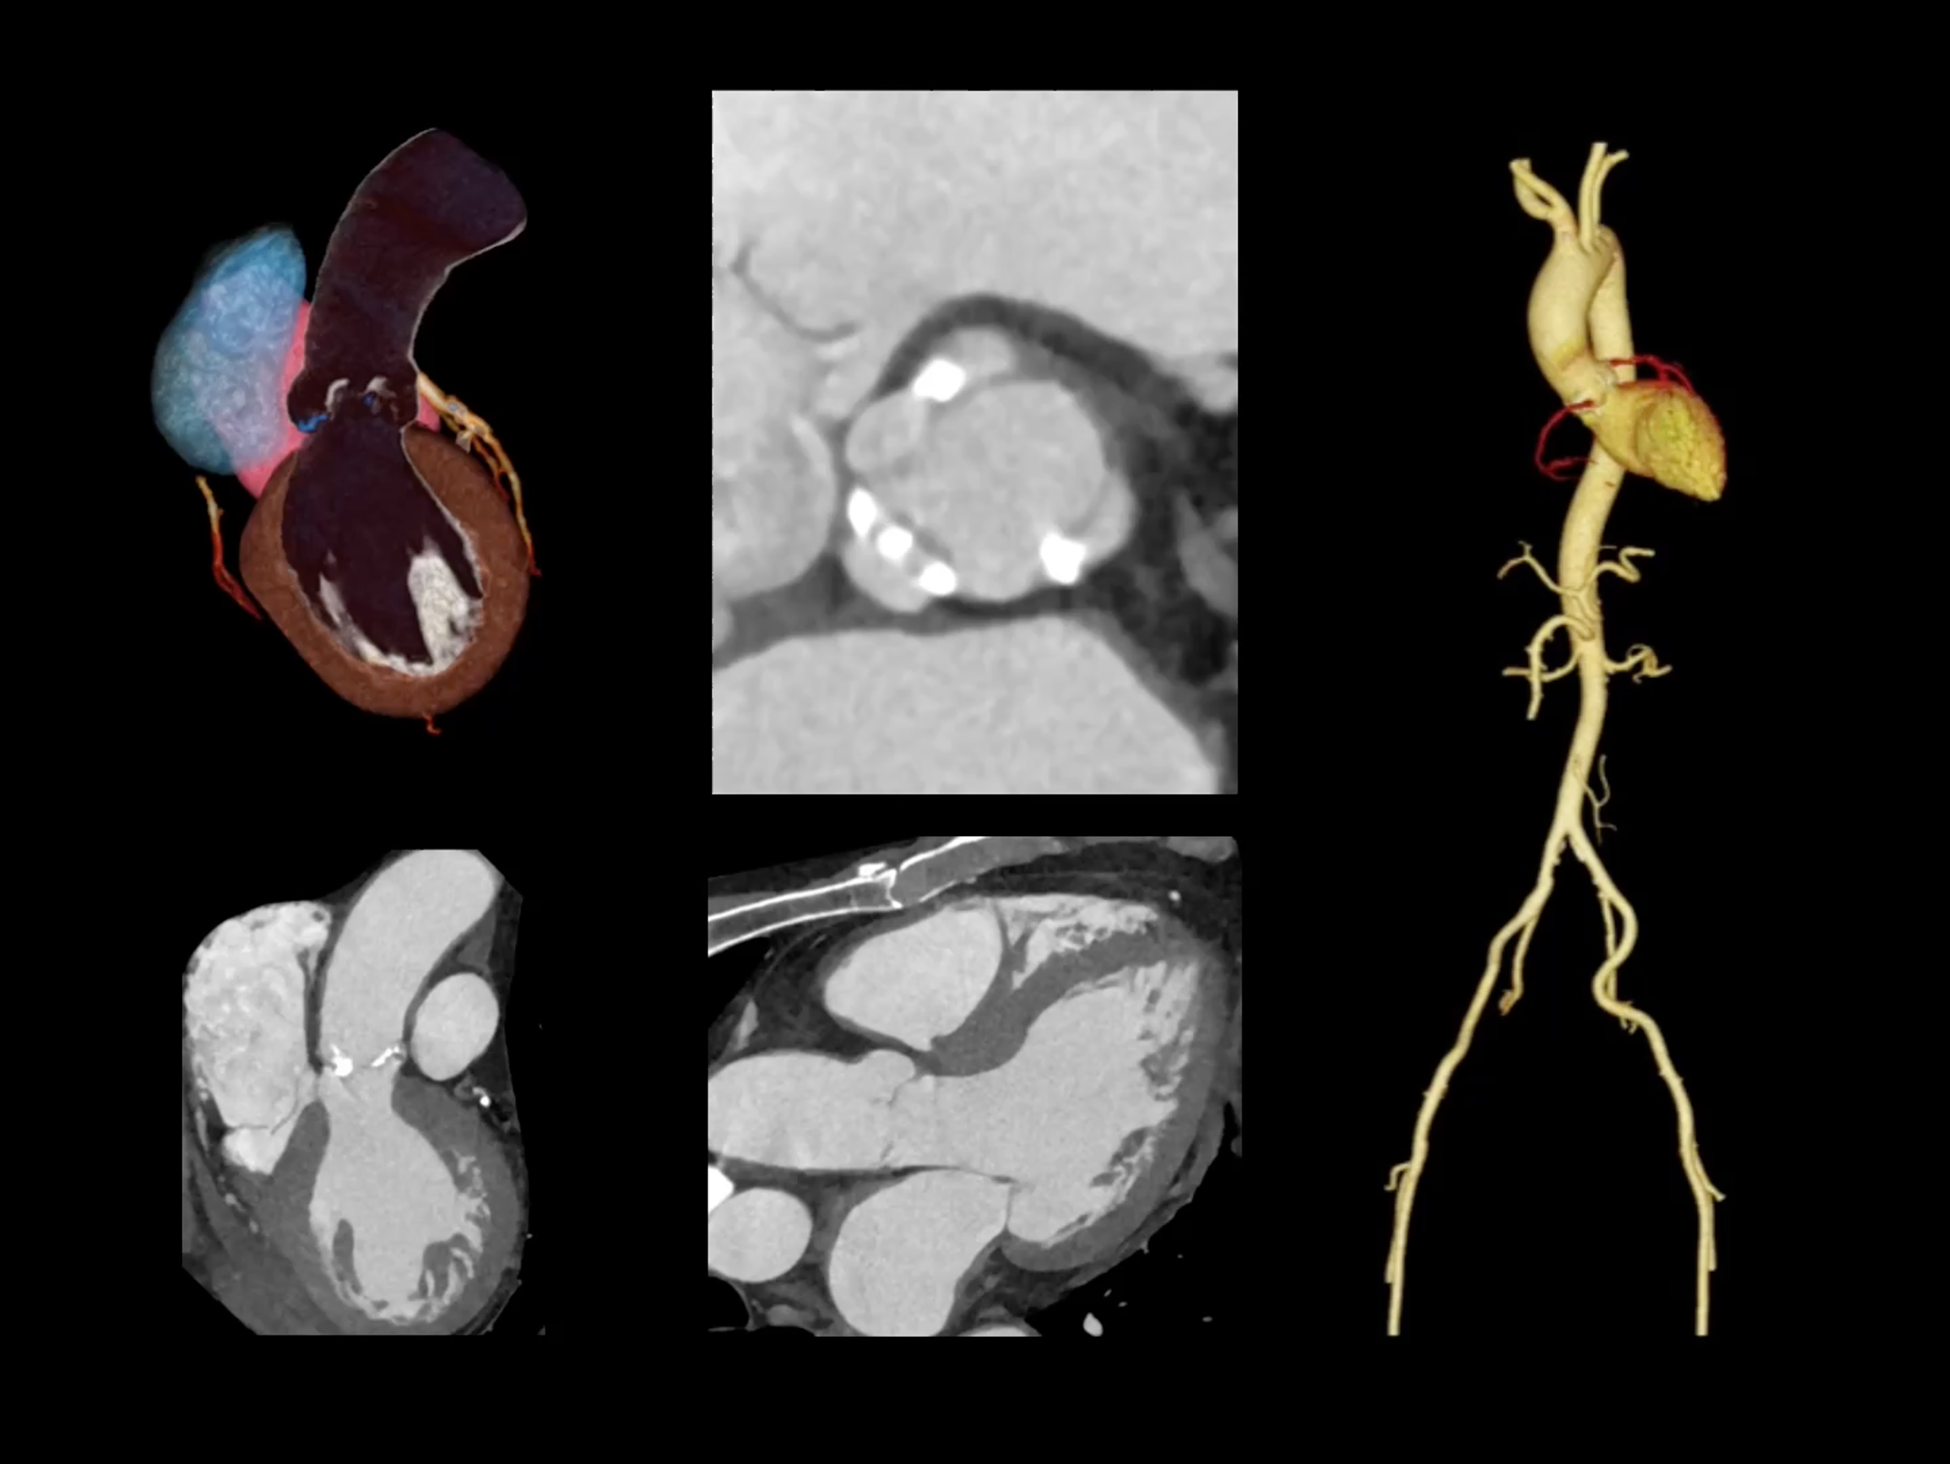

心脏成像,自由掌控

uCT SiriuX® 以 8ms 全心等效时间分辨率与16cm宽体覆盖,突破传统心脏成像局限,完整呈现搏动中的心脏结构与动态功能;配合无心电门控扫描与智能化工作流,更使心脏检查摆脱心率、配合度与操作复杂度的束缚,实现真正自由从容的成像体验,为临床功能评估提供更深层依据。

全心4D电影成像

提供全心动周期内多个时相的清晰结构成像信息,动态展示心脏结构运动变化。

全心全时相高清成像

单心动周期内的任意时相获取高质量的冠脉CTA图像,确保稳定的心脏成像效果。

单时相无心电冠脉成像

在更短单时相曝光下,实现自由呼吸、无门控的冠脉CTA成像,以低剂量、无门槛的方式,重塑心脏扫描体验。

一站式心脏多维成像

一次对比剂注射可同时获取冠脉CTA、心肌灌注和心肌延迟强化等多维图像信息。